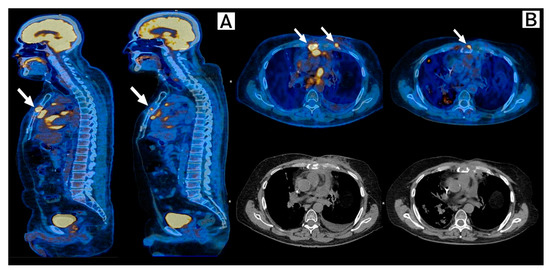

2. Case Description